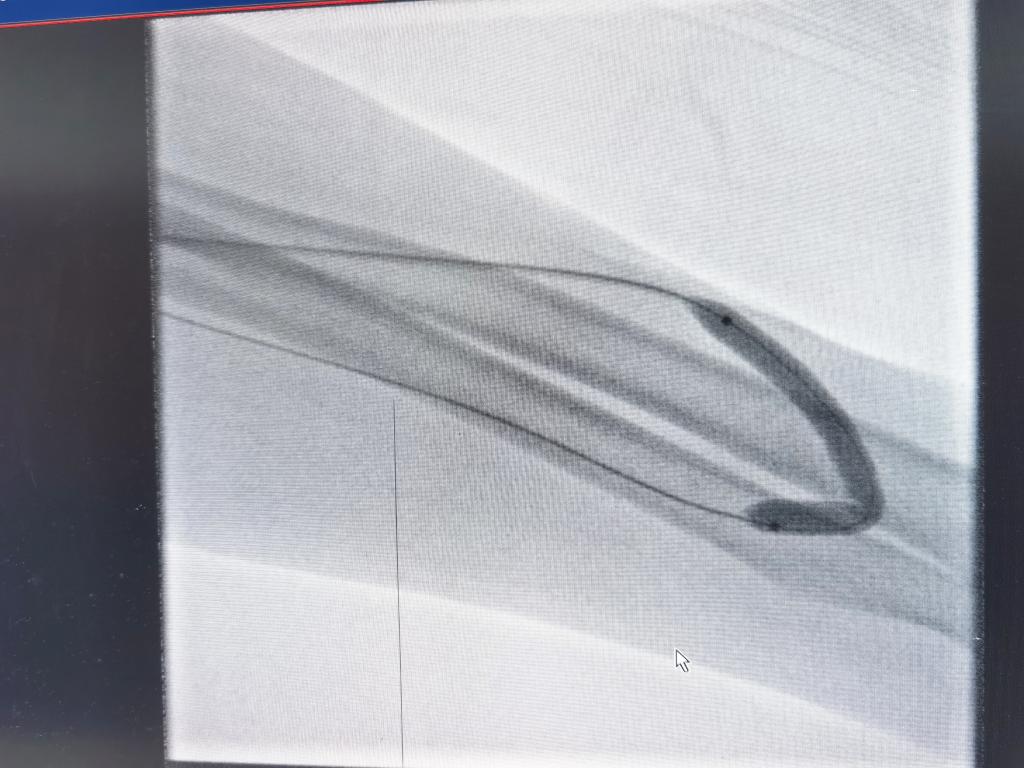

经过球囊缓慢施加压力狭窄段被撑开,“腰”消失